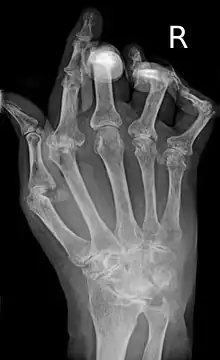

| A hand severely affected by rheumatoid arthritis. This degree of swelling and deformation does not typically occur with current treatment. | |

As the pathology progresses the inflammatory activity leads to tendon tethering and erosion and destruction of the joint surface, which impairs range of movement and leads to deformity. The fingers may develop almost any deformity depending on which joints are most involved. Specific deformities, which also occur in osteoarthritis, include ulnar deviation, boutonniere deformity (also "buttonhole deformity", flexion of proximal interphalangeal joint and extension of distal interphalangeal joint of the hand), swan neck deformity (hyperextension at proximal interphalangeal joint and flexion at distal interphalangeal joint) and "Z-thumb." "Z-thumb" or "Z-deformity" consists of hyperextension of the interphalangeal joint, fixed flexion and subluxation of the metacarpophalangeal joint and gives a "Z" appearance to the thumb.[16]: 1098 The hammer toe deformity may be seen. In the worst case, joints are known as arthritis mutilans due to the mutilating nature of the deformities.[20]

X-rays of the hands and feet are generally performed when many joints affected. In RA, there may be no changes in the early stages of the disease or the x-ray may show osteopenia near the joint, soft tissue swelling, and a smaller than normal joint space. As the disease advances, there may be bony erosions and subluxation. Other medical imaging techniques such as magnetic resonance imaging (MRI) and ultrasound are also used in RA.[20][68]